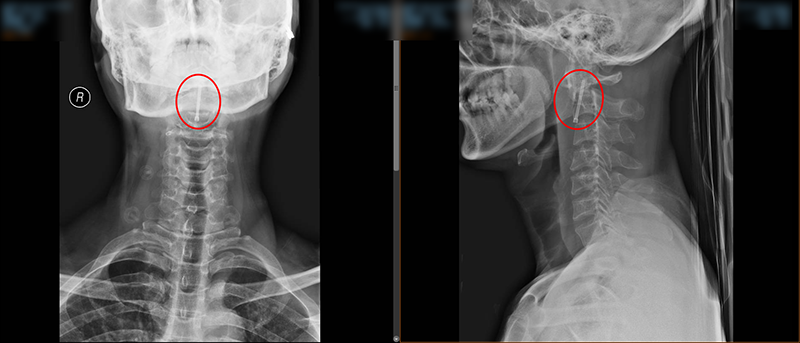

術中,脊柱外科團隊對王先生頸部重要的組織結構均進行了較好的保護,而且一次性成功的置入空心拉力螺釘固定骨折斷端。手術持續了45分鐘,術后王先生頸部疼痛明顯緩解,無神經損傷。術后給予抗炎、補液等治療,在科室專業醫療、護理團隊的共同努力下,術后復查X線顯示齒狀突復位,螺釘位置良好,目前已在支具輔助下行走活動,患者及家屬對手術效果非常滿意。

▲術后X線檢查結果